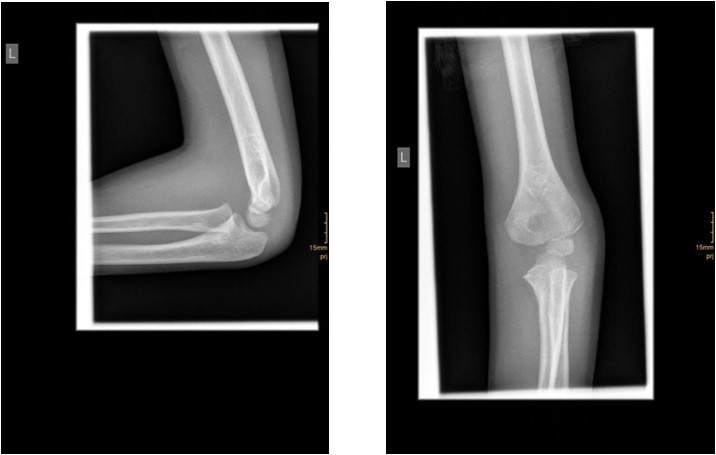

The degree of displacement may be seen on the true lateral view. In determining whether the articular hinge is intact (i.e., stage I vs. stage II), the relationship of the proximal ulna to the distal humerus is evaluated for the presence of lateral translocation. Oblique views are especially helpful in patients in whom a stage I displacement is suspected but not evident on AP and lateral views. Figure 1 and Figure 2.

Figure 1.6 year old male patient with a undislocated left lateral condyle fracture which was succesfully treated with a cast (personal collection)